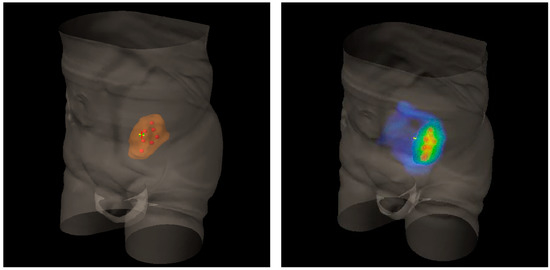

Figure 4.

The hypothesis to explain lattice radiotherapy mechanism: pink line delineates global tumor volume, the yellow line shows the necrotic core, and red spheres represent high dose regions and are approximately located at the boundary between the necrotic and normoxic areas (hypoxigenated interface) to radially elicit the bystander effect (blue arrows), accurately avoiding high dose delivery in the green strip due to the hazardous closeness of bowel (Organ At Risk: OAR).